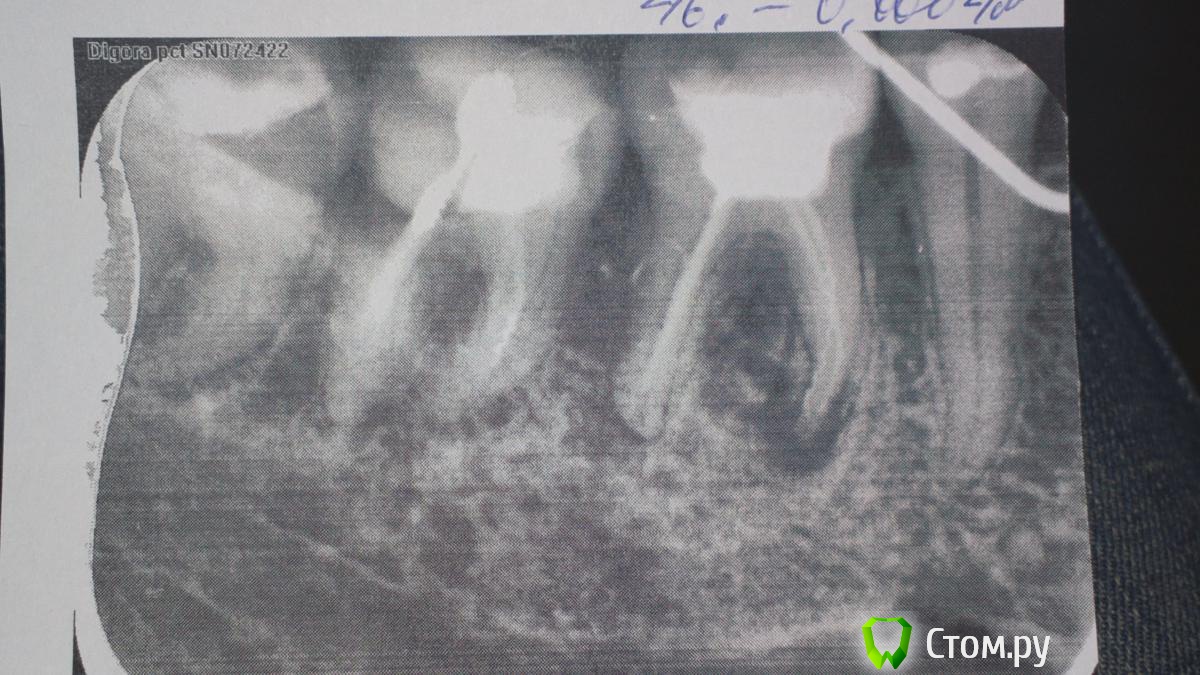

еленасп Опубликовано 10 января, 2014 Поделиться Опубликовано 10 января, 2014 Здравствуйте! Увеличился л/узул под челюстью, пошла к хирургу, врач отправила к стоматологу. У меня боль при нажатии на десну отдает в 6 зуб снизу. Сделала ренген стоматолог сказал гранулема,стоматолог- хирург сказал киста и что только удаление. Скажите пожалуйста в моем случае можно что-то сделать или обязательно удаление? И может ли от кисты увеличиться л/узел под челюстью, ныть ухо,болеть висок,непонятные ощущения в глазу и все с одной стороны где и зуб? Я так поняла что киста на корне зуба, а сейчас заметила еще на снимке темное пятно которое внизу в правом углу на снимке и оно настрораживает.Скажите пожалуйста на что это похоже? http://i069.radikal.ru/1401/43/3815deb822f9.jpg Ссылка на комментарий

DmitrySH Опубликовано 11 января, 2014 Поделиться Опубликовано 11 января, 2014 (изменено) Снимок не четкий, но если мне не изменяет зрение, то у вас там инструмент в переднем корне сломан. Лучше искать эндодонтиста работающего с оптикой. Да, с соседним тоже надо разбираться, не надо ждать пока болеть начнет. Изменено 11 января, 2014 пользователем dmitrySH Ссылка на комментарий

Bier Опубликовано 11 января, 2014 Поделиться Опубликовано 11 января, 2014 на мой взгляд тут 2 зуба пойдут на удаление.в 7ке - кариес корня, в 6ке - заместительная резорбция. Ссылка на комментарий

IvanK Опубликовано 11 января, 2014 Поделиться Опубликовано 11 января, 2014 на мой взгляд тут 2 зуба пойдут на удаление.в 7ке - кариес корня, в 6ке - заместительная резорбция.возможно,и 8 ку туда же,2 имплантата и все счастливы))) я бы сделал качественный панорамный снимок, как минимум 1 Ссылка на комментарий

Mane Опубликовано 12 января, 2014 Поделиться Опубликовано 12 января, 2014 Я тоже посмотрел и считаю что 6 и 7 на удаление и возможна одномоментная имплантация. Ссылка на комментарий